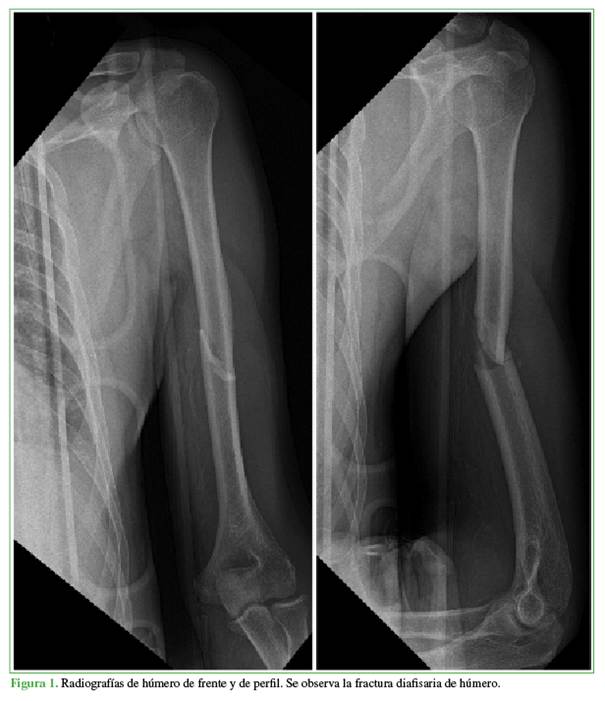

Antes de la cirugía, a todos los pacientes se les tomaron radiografías de frente y perfil que incluyeran la articulación del hombro y codo para establecer el patrón de fractura, el deseje y el desplazamiento, la clasificación, si había compromiso articular o no, y para la planificación preoperatoria (Figura 1). No se indicó, como rutina, una tomografía computarizada; este estudio se limitó a aquellos pacientes con sospecha de retraso de la consolidación o seudoartrosis.